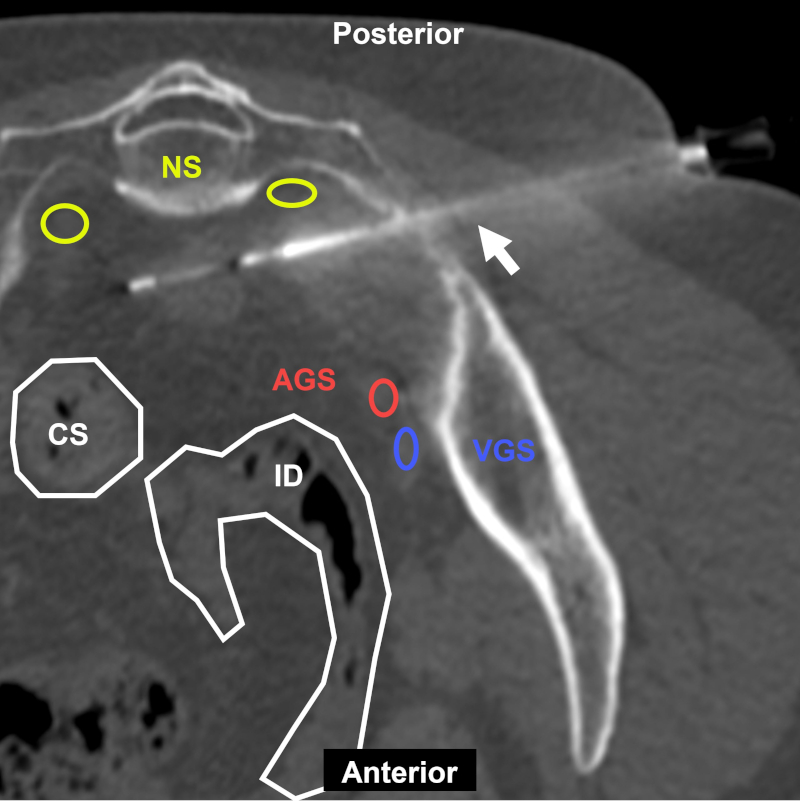

Mujer de 56 años con antecedentes de cáncer de recto con nódulo presacro en control oncológico. BP coaxial con acceso transglúteo lateral (flecha) bajo TC, reconstrucción multiplanar. Estructuras a evitar: NS: nervios sacros; AGS: arteria glútea superior; VGS: vena glútea superior; CS: colon sigmoide; ID: intestino delgado. Aguja utilizada: PL 18 G con Supercore 20 G (sistema semiautomático). Diagnóstico final: infiltración por adenocarcinoma.

Figura 21